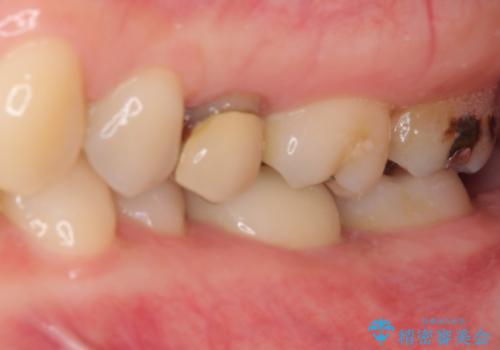

処置開始前から神経組織を部分的に除去する可能性が高いことが分かっていたため、ラバーダムなどの環境を整え、無菌的環境下にて処置を進めて行きました。

虫歯は深くまで進行しており、歯冠部後方の神経から出血が認められました。炎症を起こしている神経を除去したところ出血が治まったので、生体親和性の非常に高いセメントにて充填し、仮封をし、その日のうちに仮歯を装着しました。

後日状態を確認したところ、残された神経に異常がなかったため、フルジルコニアクラウンにて補綴治療を行いました。